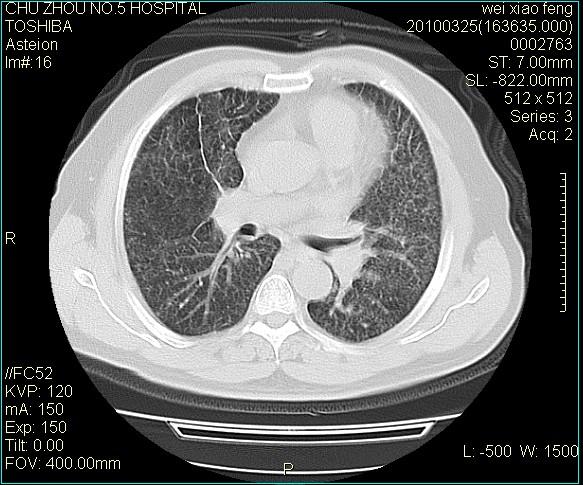

男,60岁,反复咳、痰、喘3月,加重3天。

心功能怎么样?感觉象肺淤血。

肺泡癌不除外

右肺中叶结节影为原发灶,考虑右肺中叶周围型肺癌并淋巴道转移